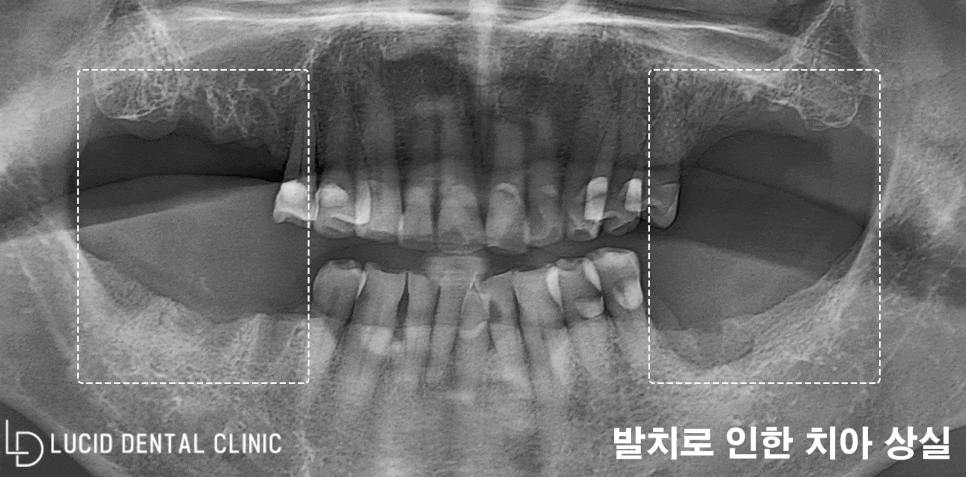

초진 당시, 환자의 구강 환경을

살펴볼 수 있도록 파노라마 엑스레이

사진을 촬영해 봤는데요

이미 치아를 발치한 지 시간이 오래 지나

치조골(잇몸뼈) 흡수가 일어나고 있었습니다.

게다가, 저작 활동을 주로 하는

어금니 치아들이 모두 소실되어

앞니로만 식사를 하고 계셨는데요

이를 지속하면 턱관절에도 무리를 주며

교합 관계 또한 비정상으로 바뀌게 되어

빠르게 처치해야 되는 상황이었습니다.